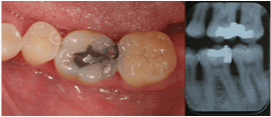

| Mandibular Right Second

Molar |

11 |

43.8% |

|

5 |

52.0% |